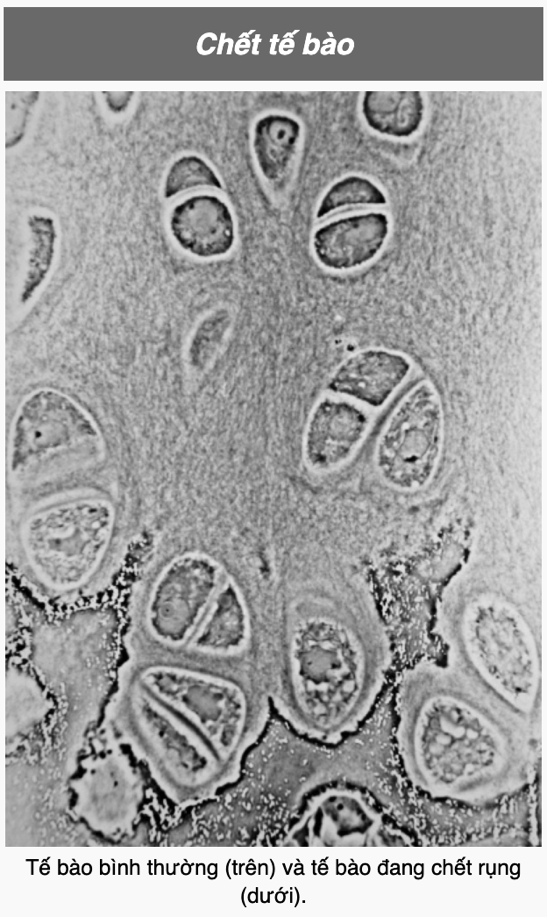

Thế nào là “chết theo chương trình” Apoptosis

“Chết theo chương trình” (apoptosis) là quá trình tế bào chết rụng phân rã thành các cấu trúc gọi là tiểu thể chết rụng. Các tiểu thể này sẽ bị thực bào xung quanh tiêu hóa trước khi các thành phần bên trong tế bào có thể tràn ra ngoài và gây hư hại cho các tế bào khác.